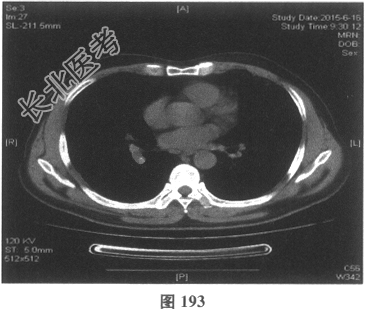

- 多项选择题4.[提示]患者应用多种抗生素治疗(第三代头孢菌素、青霉素加酶抑制剂)包括抗曲霉菌治疗无效,加用甲泼尼龙40mg静脉滴注病情好转。肺部CT检查显示病变明显改善。尿常规检查正常, 肾功能检测正常。复查肺部CT(图188~图195):示病变较前好转。Wegener肉芽肿的主要临床表现是( )